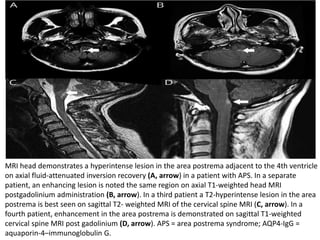

MRI head demonstrates a hyperintense lesion in the area postrema adjacent to the 4th ventricle

on axial fluid-attenuated inversion recovery (A, arrow) in a patient with APS. In a separate

patient, an enhancing lesion is noted the same region on axial T1-weighted head MRI

postgadolinium administration (B, arrow). In a third patient a T2-hyperintense lesion in the area

postrema is best seen on sagittal T2- weighted MRI of the cervical spine MRI (C, arrow). In a

fourth patient, enhancement in the area postrema is demonstrated on sagittal T1-weighted

cervical spine MRI post gadolinium (D, arrow). APS = area postrema syndrome; AQP4-IgG =

aquaporin-4–immunoglobulin G.